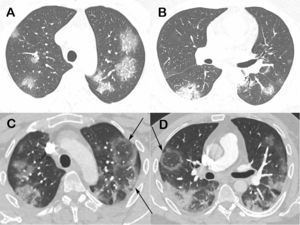

Real-time reverse-transcription polymerase chain reaction of a nasopharyngeal sample tested positive for the SARS-CoV-2, confirming the diagnosis of COVID-19. A chest computed tomography obtained 2 days after symptom onset showed bilateral ground-glass opacities (Fig. 1A and B). A new CT performed 3 days later demonstrated multiple RHS (Fig. 1C and D).

Chest computed tomography images of a 48-year-old man with confirmed COVID-19 pneumonia. Images obtained at the levels of the upper (A) and lower (B) lobes 2 days after symptom onset show bilateral round and oval ground-glass opacities. Enhanced images (C and D) obtained at the same levels as A and B 3 days later show multiple reversed halo signs (arrows) in both lungs.